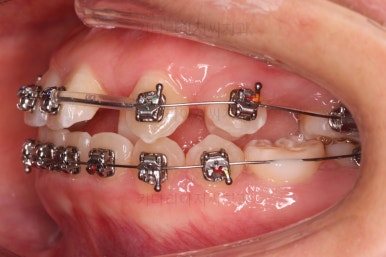

미니스크류가 등장했네요.

아랫니는 아무 생각 없이 당기기 해주면 앞니가 너무 들어가 입이 합죽해질 수 있으니 앞니가 들어가는 양을 조절하기 위해서 미니스크류를 사용해주어요.

적절한 시기부터는 어금니만 100% 앞으로 당겨와야 했기 때문이죠.

비슷한 방법으로 계속 당기기를 해줍니다.

이 과정이 매우 어렵고 시간도 많이 걸려요.